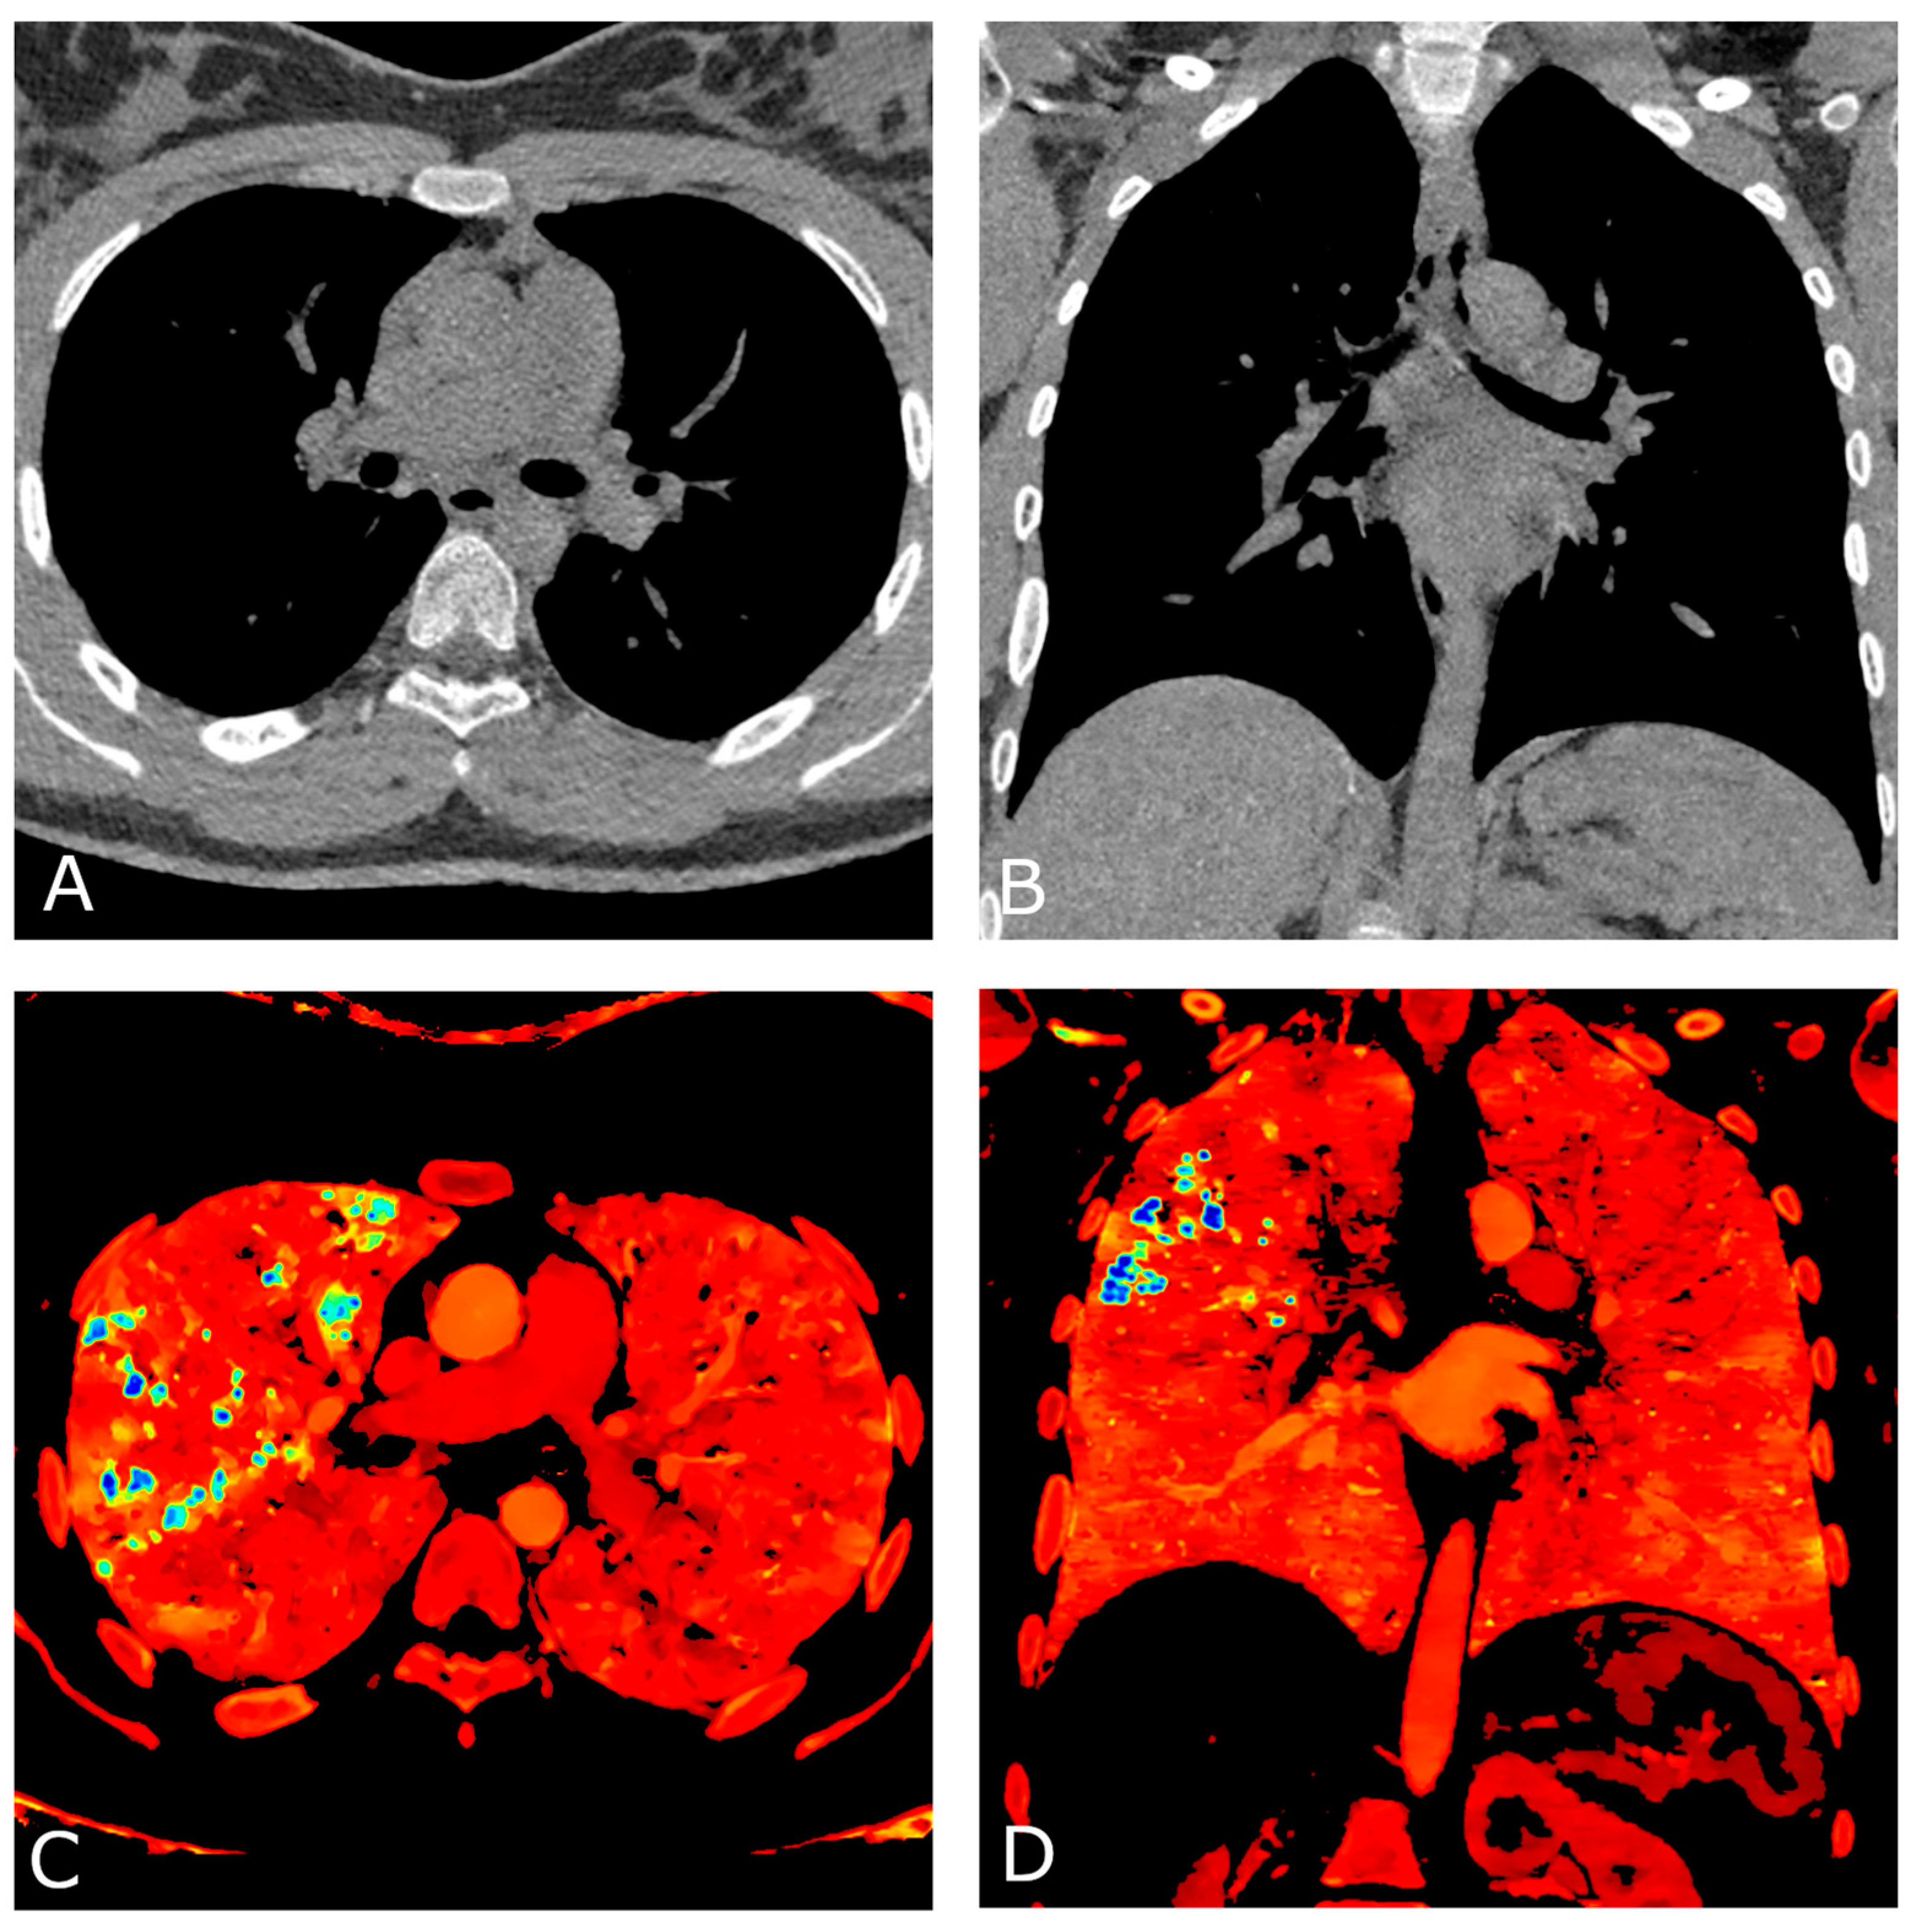

A comprehensive spectral evaluation was performed to characterize the high-density nodules. Firstly, virtual non-contrast reconstruction was obtained to derive the pre-contrast images (Figure 2A,B). All the lesions were removed along with the iodinated contrast medium, suggesting high Z number of the material and excluding the presence of calcium-containing lesions (Z = 20). Regions of interest were placed within the micronodules, in the sternum and in the aorta to investigate differences in attenuation (Figure 3). Despite the curves showing similar patterns, increasing at low energy levels (i.e., 40 keV), the lung nodules had the highest profile, even when compared to the iodine attenuation curve. Color-coded reconstruction maps based on Z-effective number also revealed that the lung nodules were composed of a material with higher Z number than iodine (Figure 2C,D). A careful review of the patient’s medical record showed that the patient had undergone a barium-swallowing study in another institution two years earlier. This study was interrupted due to the transit of a considerable amount of contrast material into the right bronchial tree through a small tracheoesophageal fistula (Figure 4). Patient’s medical history, together with spectral information, allowed for diagnosis of barium lung granulomas related to a previous swallowing study.

Figure 2.

Chest CT angiography with ECG gating performed on a dual-layer DECT platform. Axial (A) and coronal (B) virtual non-contrast reconstruction (VNC) images. All pulmonary lesions are removed along with the iodinated contrast medium, suggesting similar Z number of their composition material with the iodinated contrast agent. Axial (C) and coronal (D) color-coded reconstruction maps based on Z-effective number, depict higher values of the pulmonary nodules (blue) compared to iodinated structures (green), consistent with a higher Z number of barium (Z = 56) than iodine (Z = 53).